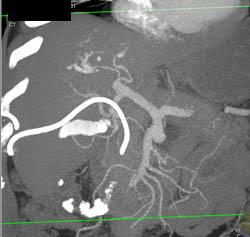

Cholangiocarcinoma